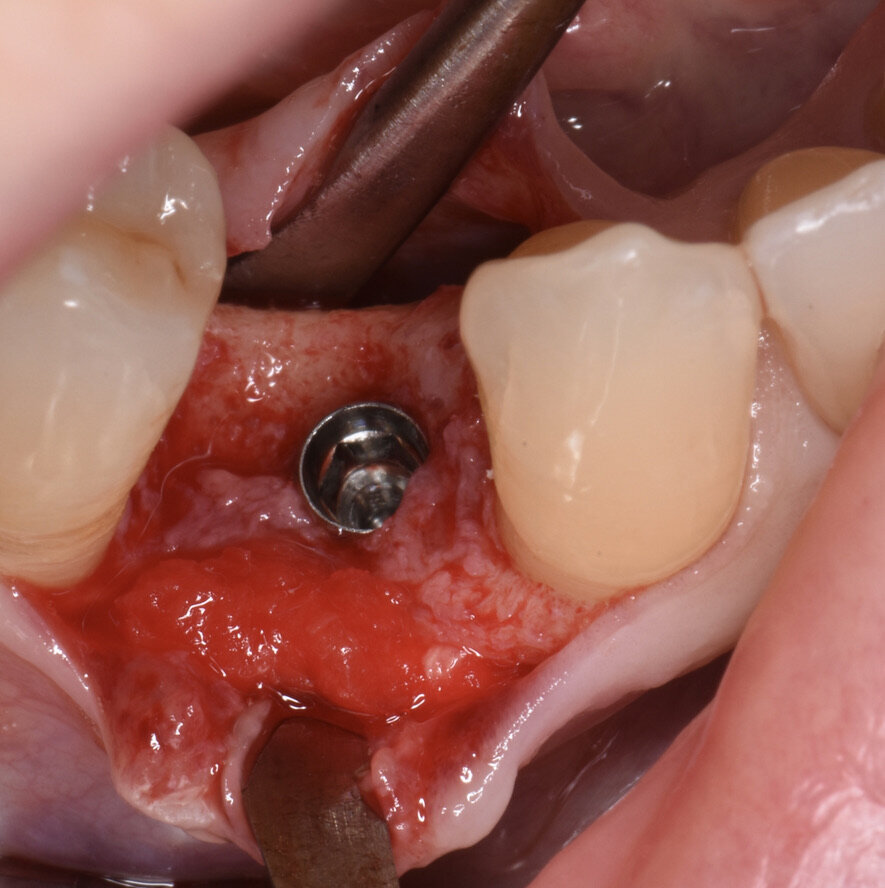

Prima dell’estrazione (S0), ad ogni paziente è stata eseguita una scansione intraorale tramite scanner iTero (Align Technology) (Fig. 2), e le scansioni sono state archiviate. A distanza di 2 mesi dall’estrazione è stato creato un lembo vestibolare a busta, a mezzo spessore, è stato inserito l’impianto nel sito (Figg. 3, 4) ed è stata posizionata la matrice in collagene suino volumetricamente stabile Geistlich Fibro-Gide (Geistlich Pharma), stabilizzandola al periostio con due punti di sutura riassorbibili interni (Fig. 5)7. Il lembo è stato quindi suturato con suture non riassorbibili e punti sospesi in modo da garantire la chiusura primaria e mantenere la matrice sommersa ma non compressa (Fig. 6).